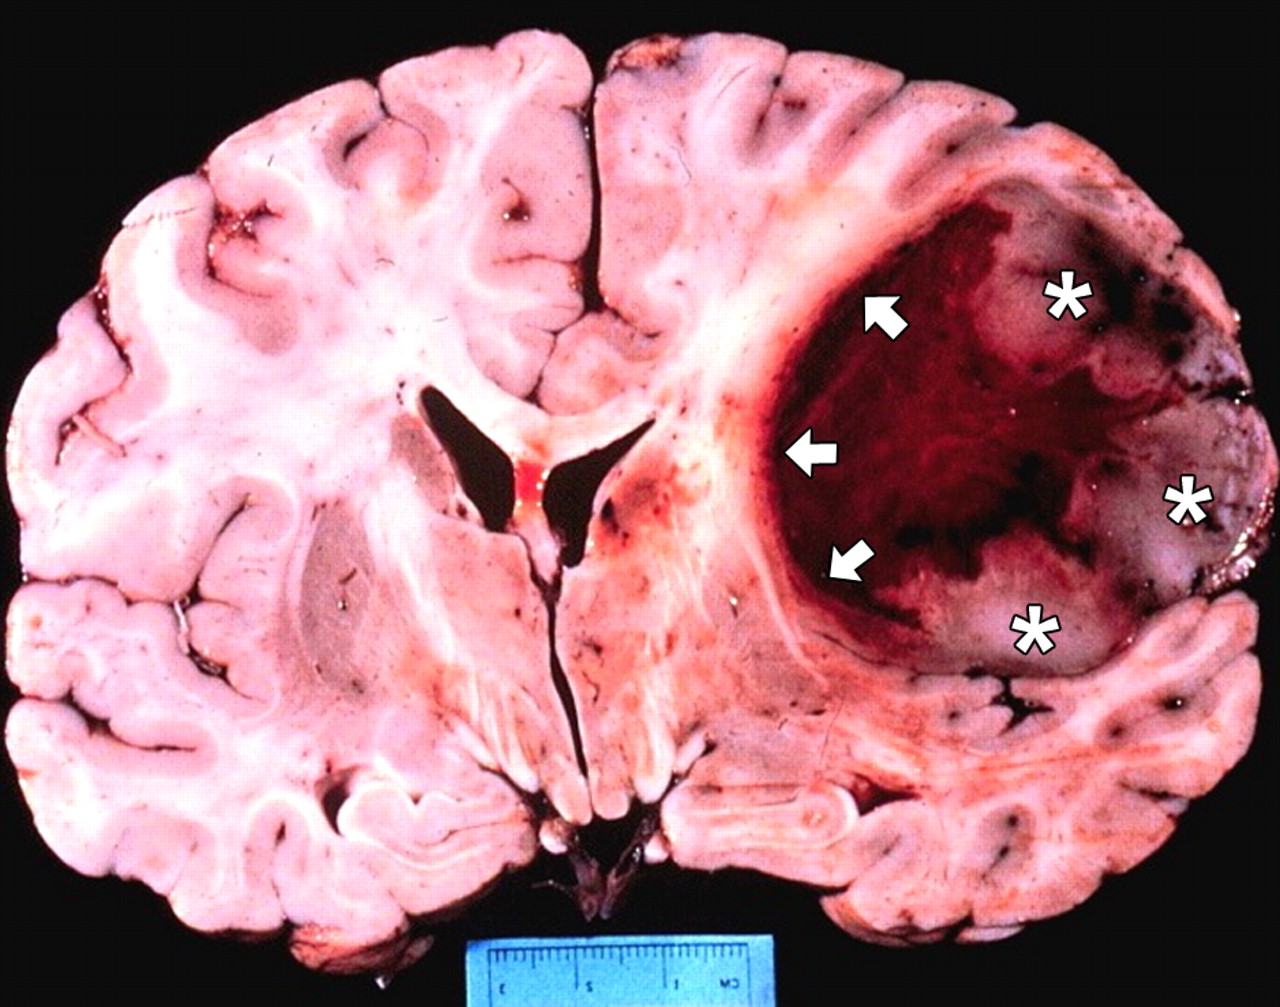

Glioblastoma: scoperta la mutazione genetica che lo causa

Una ricerca condotta da ricercatori della Columbia University di New York, in collaborazione con ricercatori italiani dell’Istituto Neurologico Carlo Besta, ha identificato una nuova mutazione genetica che è la causa del glioblastoma. L’alterazione aumenta l’instabilità del DNA genomico variando il numero dei cromosomi presenti nelle cellule, caratteristica fondamentale del glioblastoma e di altri tumori. La mutazione genetica è determinata dalla fusione di due geni FGFR e TACC. Quando il prodotto della fusione raggiunge cellule che presentano un’altra mutazione derivante dall’alterazione di INK, geni che controllano la proliferazione delle cellule,si crea un glioblastoma. La malattia può insorgere a tutte le età, ma in particolare tra i 55/65 anni. Nonostante l’intervento chirurgico, la radio o chemio terapia, la sopravvivenza dei pazienti è ancora molto bassa. Poichè questi tumori possono essere inibiti da alcuni farmaci sperimentali, la scoperta ha la potenzialità di trasformarsi in un nuovo tipo di trattamento mirato ai tumori che presentano la fusione derivante dalla mutazione genetica. la ricerca è stat pubblicata sulla rivista Science.